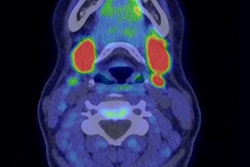

FCH-PET image of an ectopic mediastinal parathyroid adenoma (arrows) on (A) sagittal and (B) axial view fused with simultaneous MRI. This patient had previously undergone a bilateral neck exploration, which had failed to localize a left lower gland. Ultrasound, sestamibi, and 4D CT were all negative. After FCH-PET localization, a robot-assisted left thoracoscopic approach was employed to resect the gland from the aortopulmonary window. Follow-up blood work 8 months after surgery confirmed normalization of calcium. Image courtesy of Surgery.Graves and colleagues found that F-18 FCH-PET localized at least one cancer lesion in 93% of patients overall and in 91% of patients with previously negative imaging, leading to a change in preoperative strategy in 60% of patients. Of 76 patients who underwent parathyroidectomy, 58 (77%) had laboratory data at least six months afterward, with 55 out of 58 of these patients (95%) demonstrating cure.